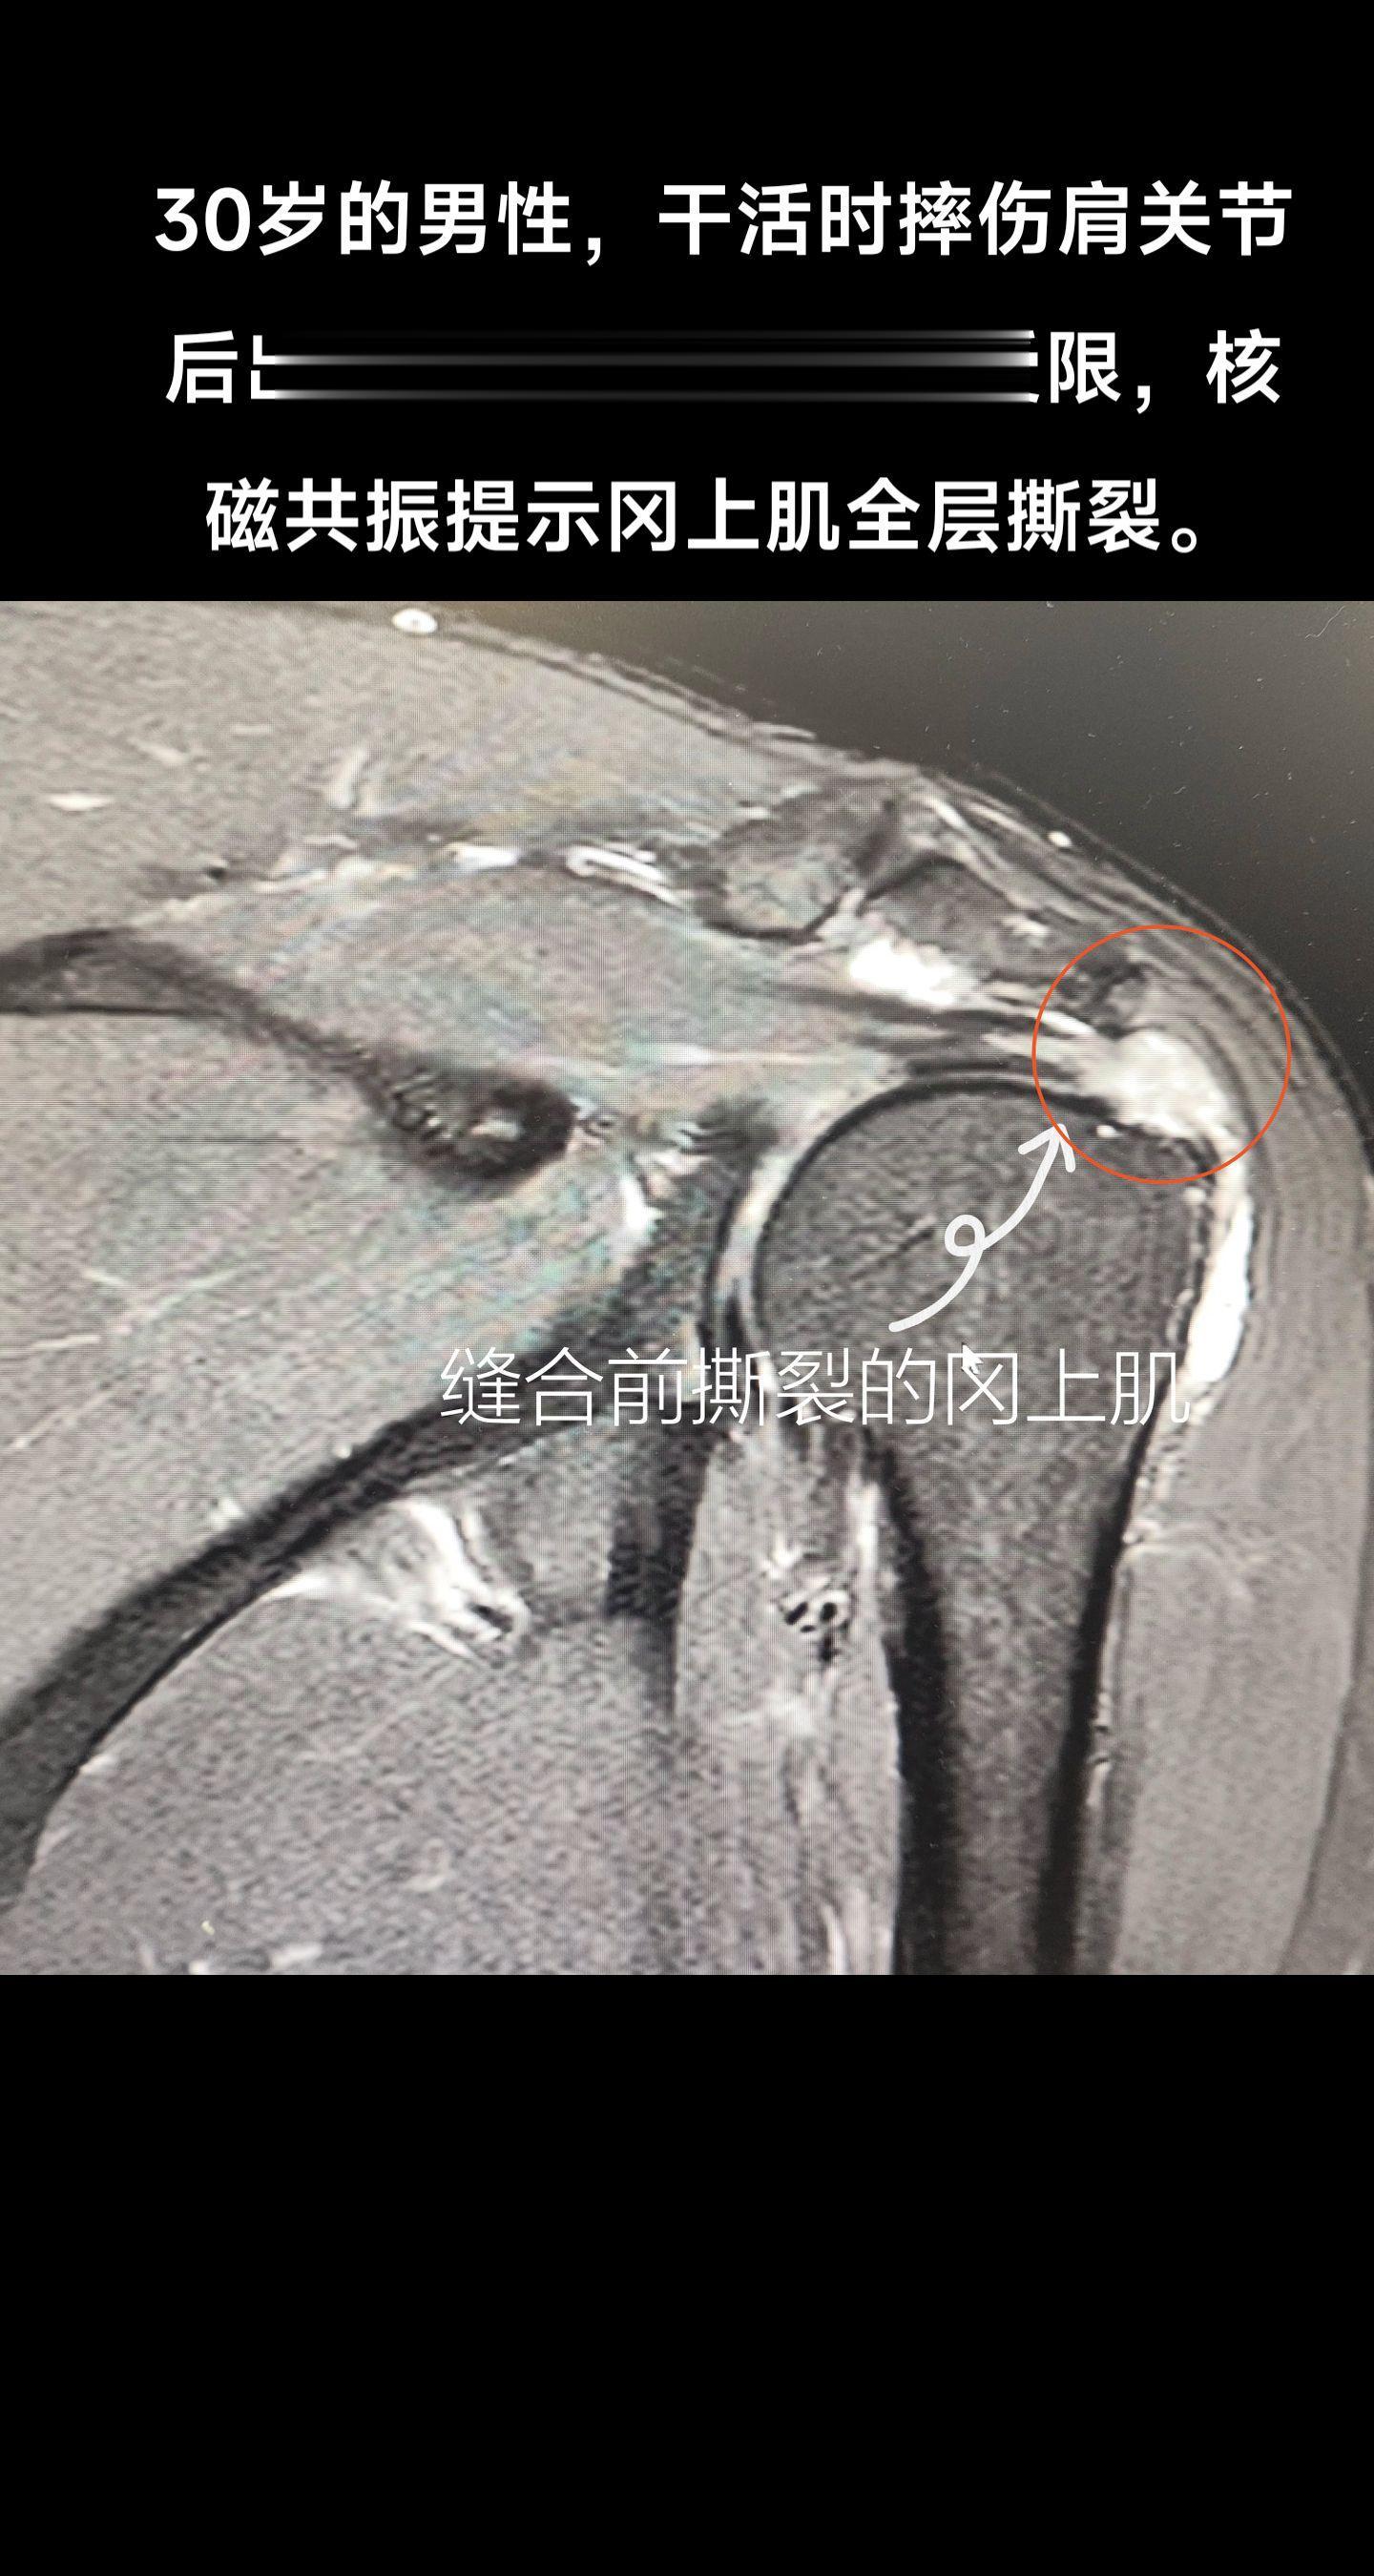

肩袖撕裂。